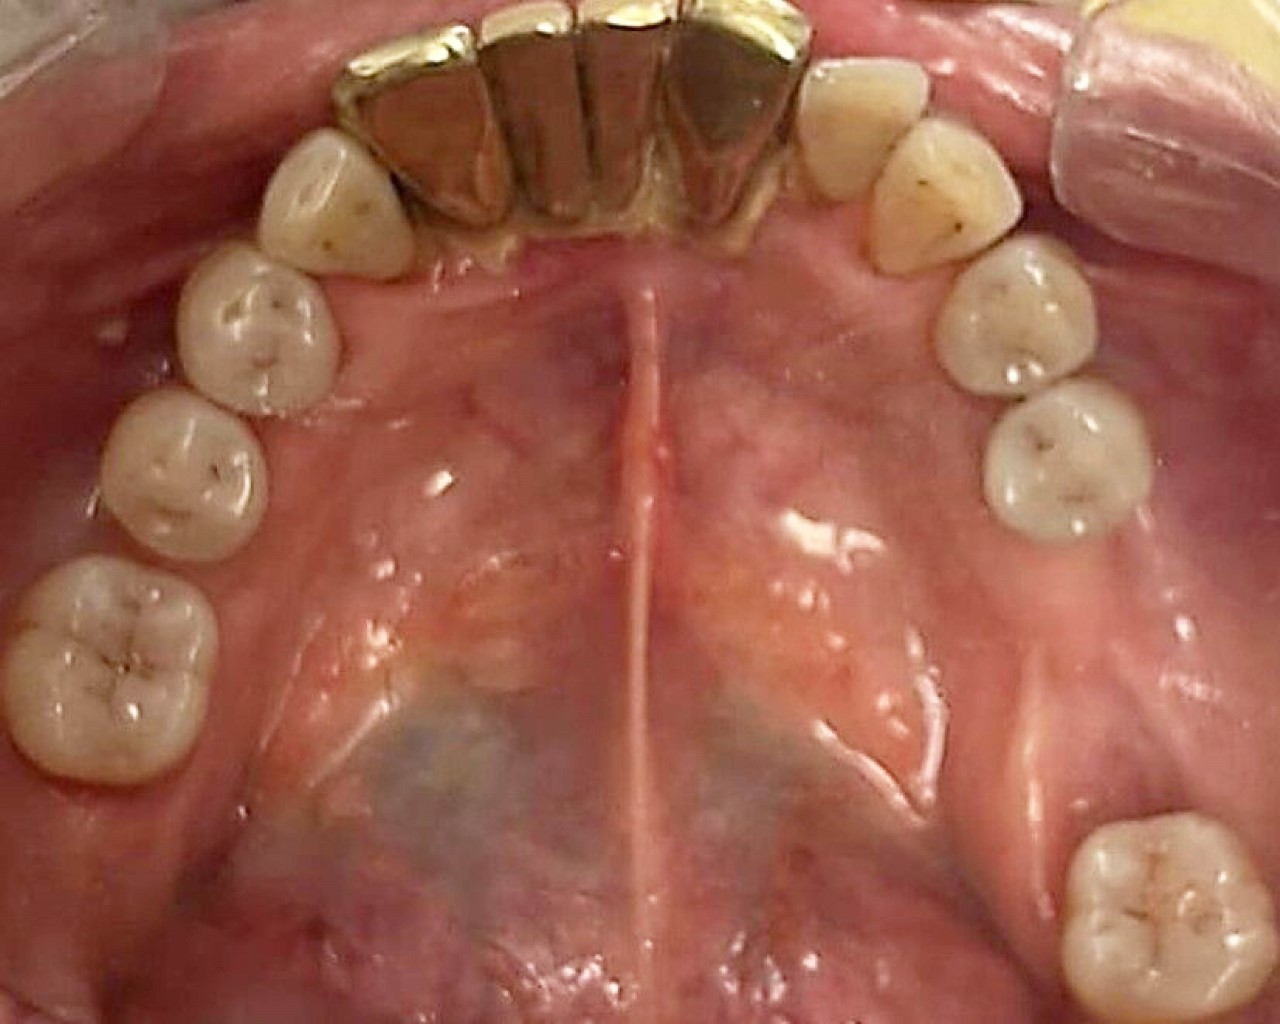

En la ortopantomografía se reveló una zona osteólisis de bordes irregulares, delimitada por un borde radiolúcido que denota presencia de secuestro óseo al mismo nivel de la secreción, sugerente de MRONJ (Figura 1).

Figura 1